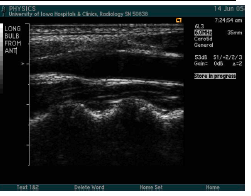

what windows are used when imaging the carotid?

Anterior

Lateral

Posterior

what is the carotid imaging protocol?

Begin with transverse imaging to determine vessel orientation and presence of plaque.

Continue with longitudinal images.